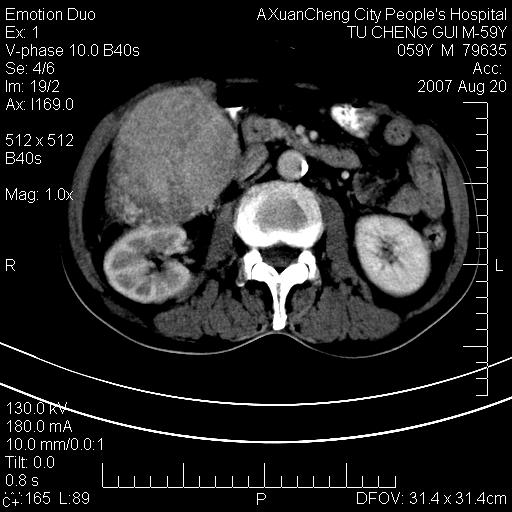

增强

患者有肝硬化,平扫病灶呈不均性低密度,增强呈快尽快出表现,内见更低密度灶,静脉期延迟期呈低密度符合肝癌表现,内低密度为坏死改变并少量胸腹水。

动脉期肝右动脉粗细不均,走行有点迂曲,门脉期门脉右支有点受侵,并且中心有坏死,呈快进快出,符合肝癌

典型的肝癌(巨块型)、腹水---增强呈快进快出强化

肝右叶巨块型肝癌伴少量腹水.双侧少量胸腔积液.